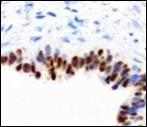

Figure 12.Cutaneous ciliated cyst with nuclear immune reactivity to oestrogen receptors (19).

Smooth muscle actin (SMA) is immune non reactive, thereby suggesting an absence of smooth muscle within the cyst wall. Intense immune reactivity can be cogitated within epithelial nuclei for oestrogen receptors (ER) and progesterone receptors (PR). Aforesaid immune reactions are indicative of Mullerian origin of cutaneous ciliated cyst.